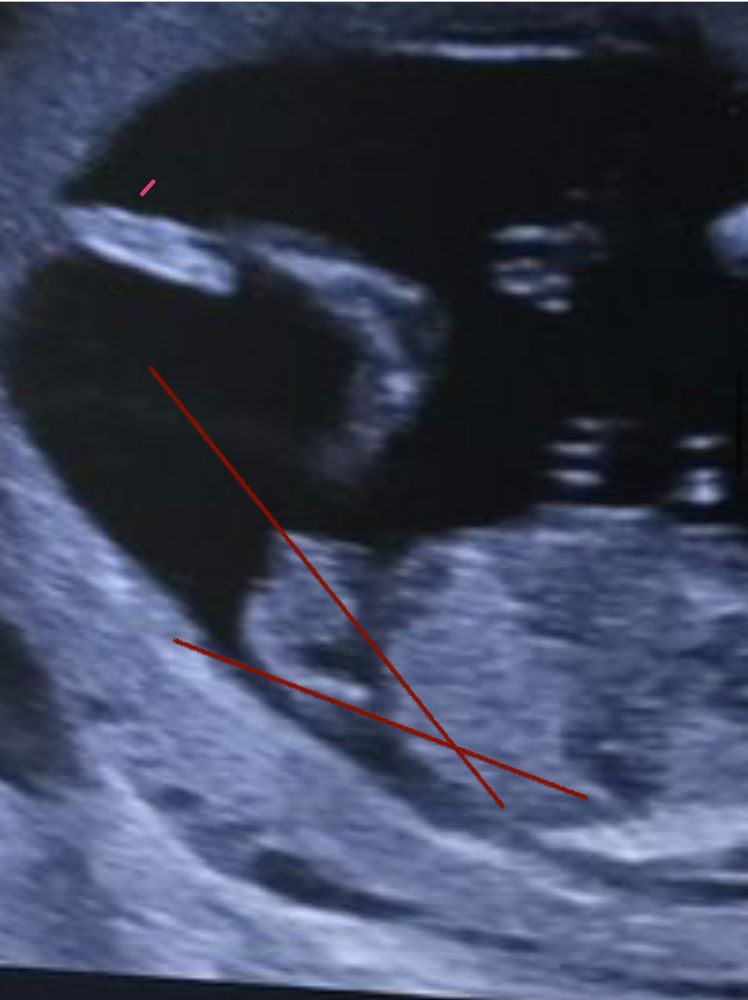

Дарья, вот ваш угол полового бугорка, прям как по книжке Изображение